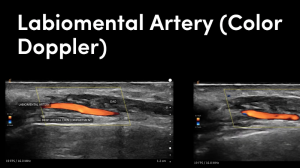

We have been working blindly for many years. And now we can confidently train you to be able to fully map out the face in terms of arteries and much more. We can measure depths of arteries and diameters and much much more.

Our course is a fully comprehensive course that not only provides you with the only ultra high frequency portable ultrasound in the world but also teaches you exactly how to use it to its best effectiveness. Over this two day course. You will cover off complications to the very highest level. Along with the most in depth anatomy training available anywhere.